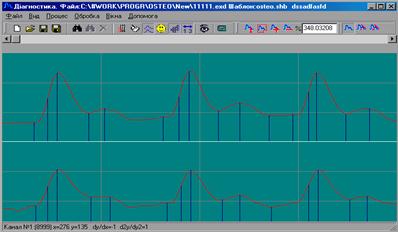

Переміщення по навігатору відбувається з допомогою клавіатури або маніпулятора "миша". Після вибору певного елемента 3-го рівня навігатора ("До сеансу" або "Після сеансу") можна приступати до зняття ФПГ даних.

Реєстрація ФПГ:

Після вибору певного

елемента навігатора (як, наприклад зображено на рисунку 8.3 ви можете здійснити зняття даних,

Регулюючи силу притиснення датчиків у міжхребетних западинах і вибираючи коефіцієнт підсилення датчиків (для зовнішнього знімного пристрою це регулятор на передній панелі), досягнути появи стійких ПХ із максимальним рівнем амплітуди сигналу в двох каналах [19].

Знята ФПГ автоматично записується в пам"ять для обраного елемента навігатора.

Зняті ФПГ зберігаються у виді, представленому на рисунку 8.5. Для перегляду значень ФПГ використовується інформаційна панель, що знаходиться під графіками і містить інформацію про координату, значення і похідні ФПГ у місці, де знаходиться курсор маніпулятора "миша".

Пересування по ФПГ здійснюється за допомогою смуги прокручування, розташованої над графіками.

Для розрахунку основних параметрів пульсової хвилі, необхідно розставити маркери в характерних точках ФПГ як показано на рисунок 8.6. Для цього виберіть пункт "Обробка - Розставити маркери".

Рисунок 8.6 – Розміщення маркерів

В даній роботі розглянуті принципи взаємодії оптичного випромінювання з біотканиною, що дозволяє стверджувати про доцільність використання фотоплетизмограми (ФПМ) для оцінки мікроциркуляцій крові. Зняття двох ФПГ з двох розташованих рядом ділянок шкіри дозволяє відкинути такі фактори як колір, температуру і деколи геометрію поверхні шкіри. Абсолютний та порівняльний аналіз двох ФПГ дозволяє стверджувати про порушення кровоносної системи, присутніх в одному з каналів.